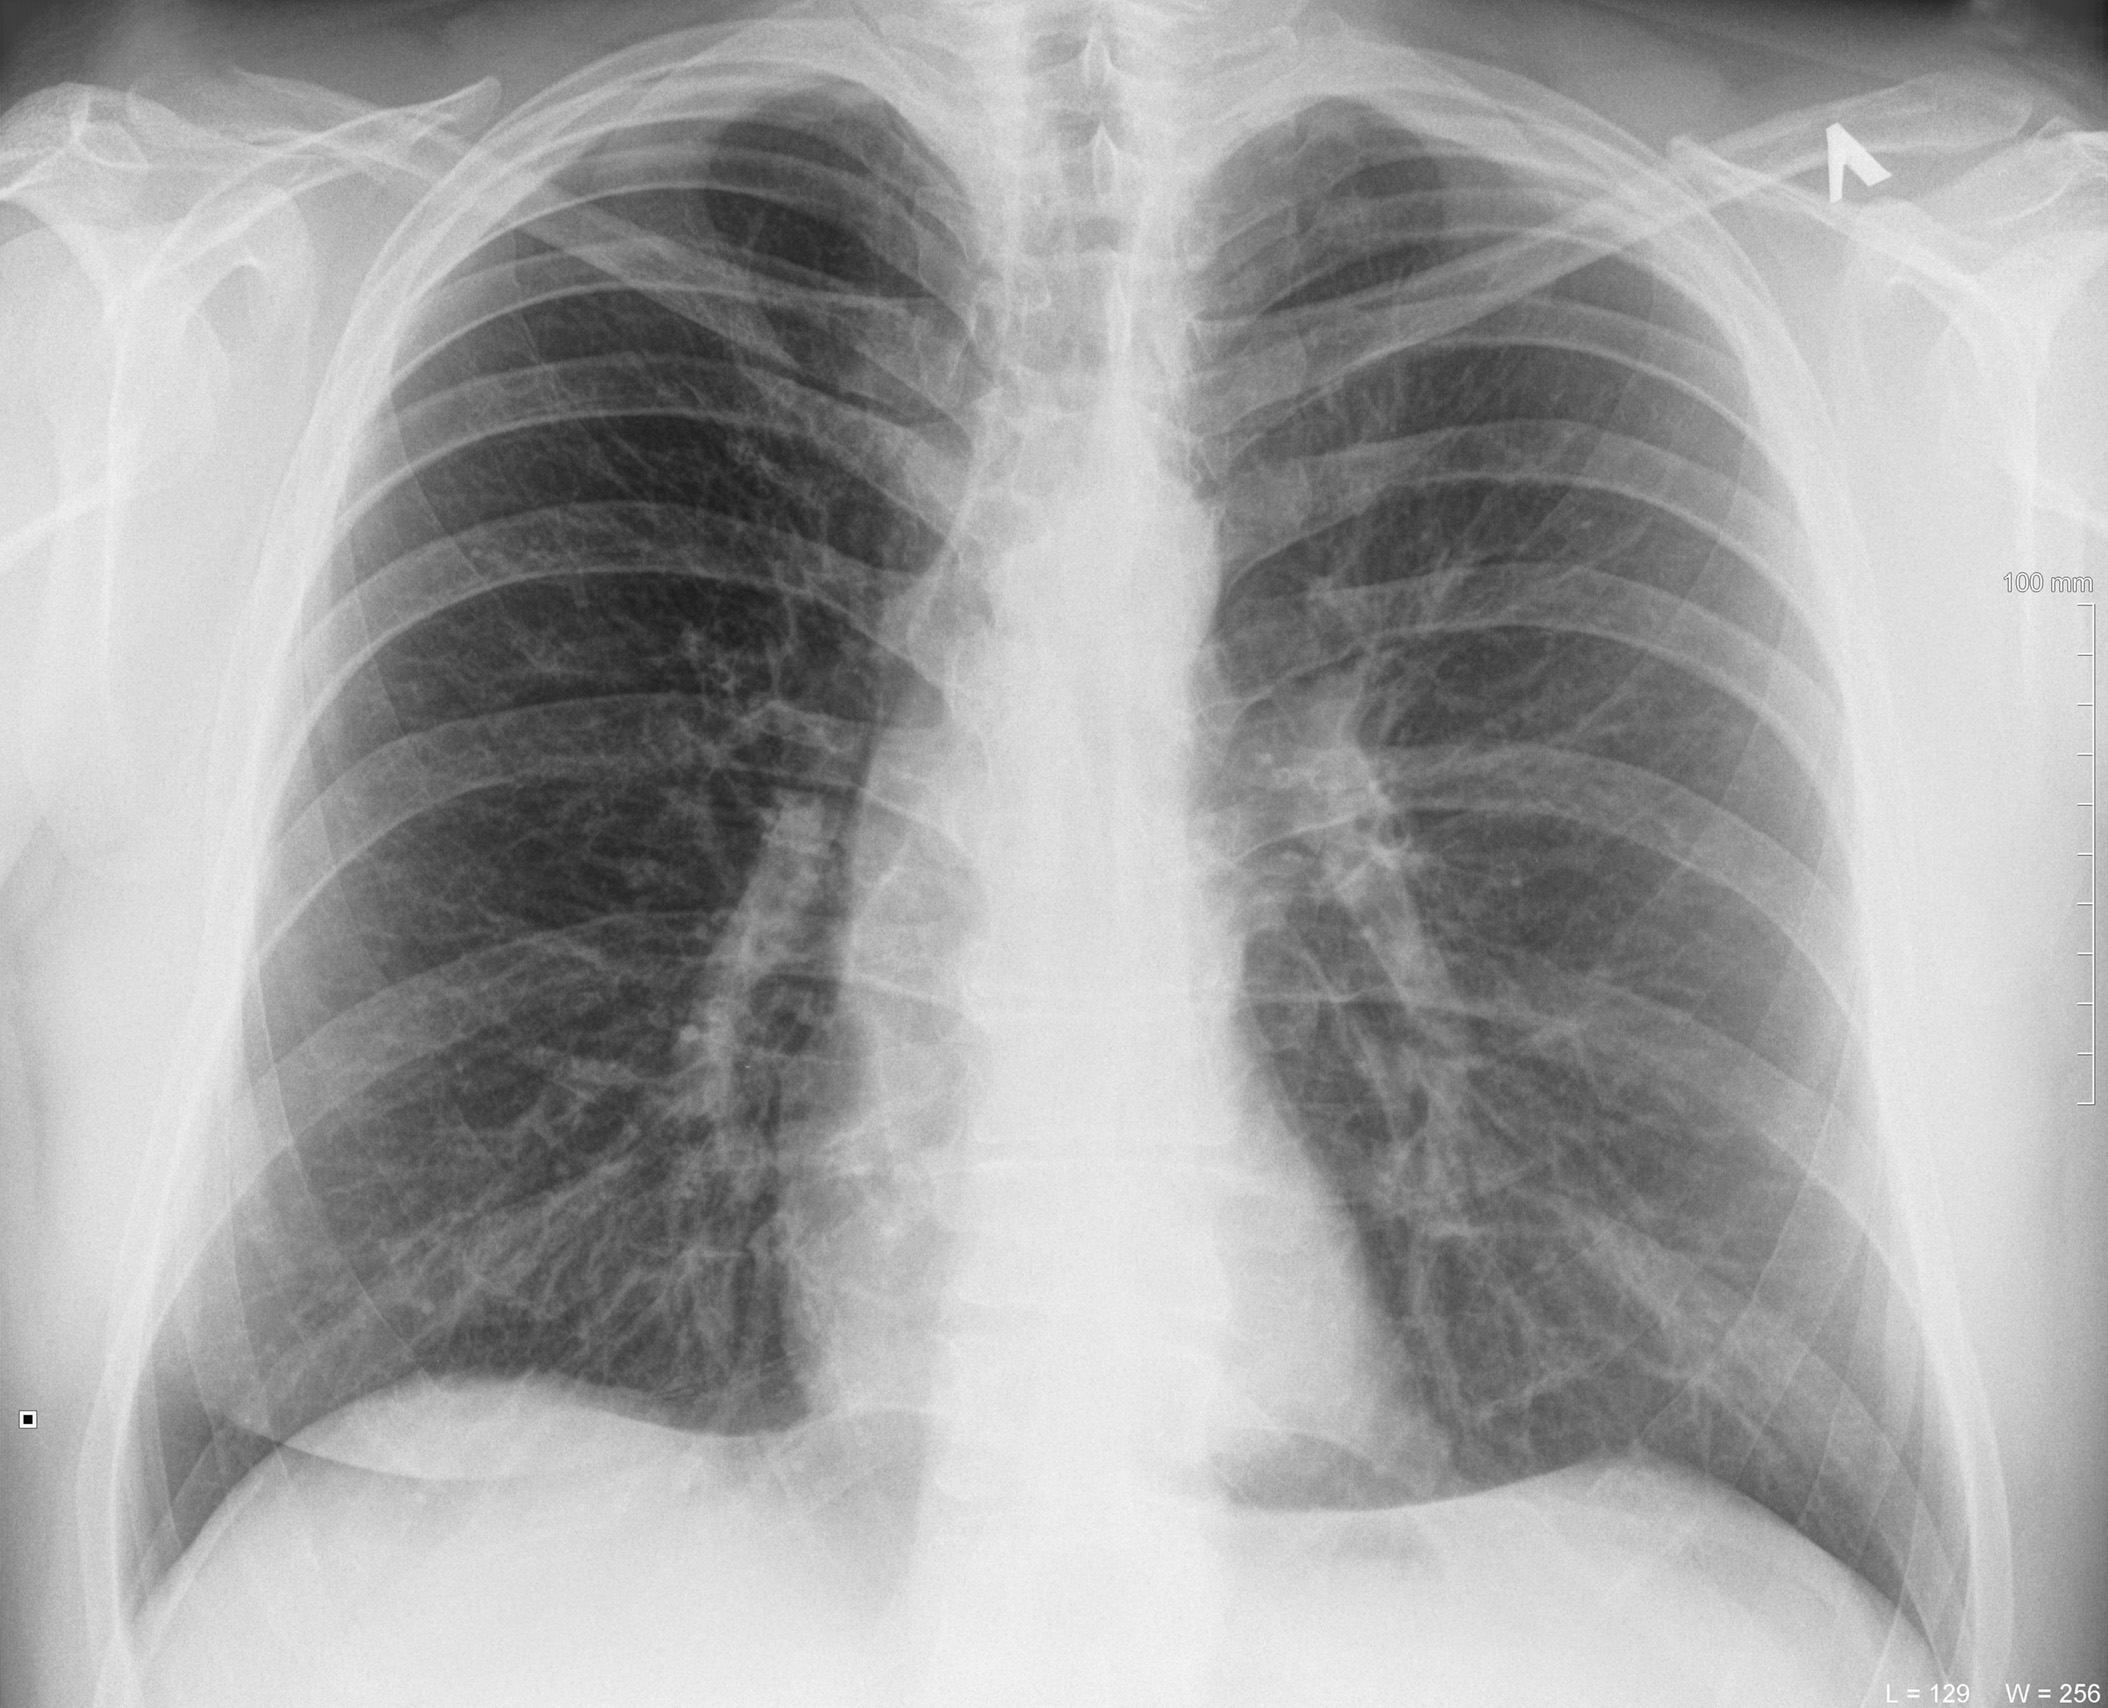

Фотографии, демонстрирующие обнаруженное усиление легочного рисунка

Раздел: Фотодневник открытий